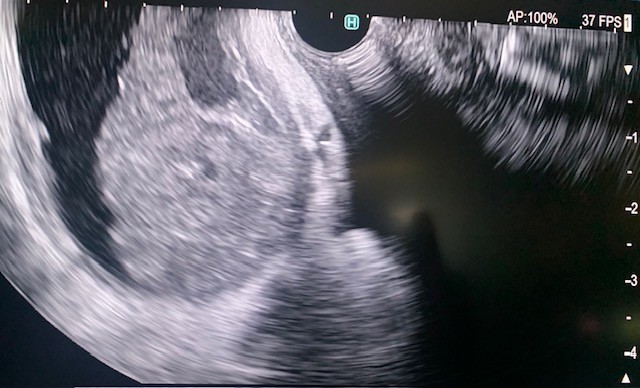

The side-viewing duodenoscope (Olympus) was passed to the duodenum and the major ampulla appeared normal in the second part of the duodenum. A Jagtome Rx 39 (Boston Scientific) with a loaded revolution Jagwire 0.025 was used to cannulate the common bile duct. Cholangiogram showed a very small bile duct, cystic duct and that the gallbladder was filled with a large amount of sludge. Sphincterotomy was performed over the guidewire, and a black pigmented stone was dislodged from the ampulla. Then the Jagwire was maneuvered into the gallbladder the cystic duct was dilated using a Hurricane balloon 4mm x 4cm (Boston Scientific) (Fig 3). A 7 french 15-cm double pig-tail plastic stent (Boston Scientific) was deployed, the proximal curled pigtail in the duodenum and the distal pigtail end was in the gallbladder through the ampulla (Fig 4). The contrast from the gallbladder was subsequently emptied out of the stent showing patency.

Figure 4. Fluoroscopic imaging of the distal end of the stent deployed in the gallbladder.

Figure 4